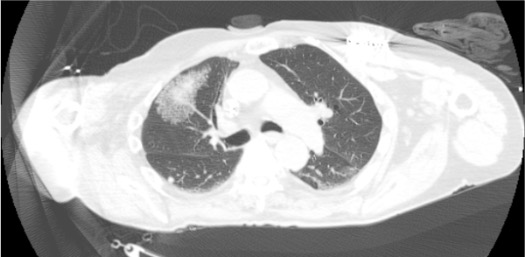

View needle in target lesion

CT showing biopsy needle positioned in pulmonary lesion